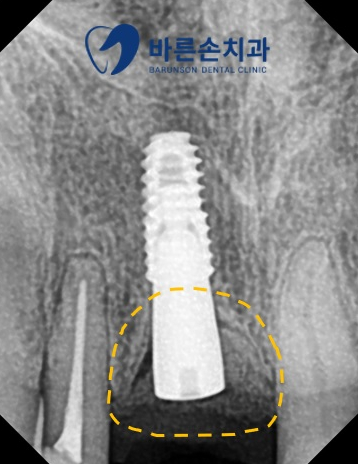

임플란트 수술 후 엑스레이 사진입니다

점선 표시에 치조골 이식이 안정적으로 잘 진행된 것이 보이며

임플란트 또한 안정적인 위치에 식립이 된 것을 확인할 수 있습니다^^